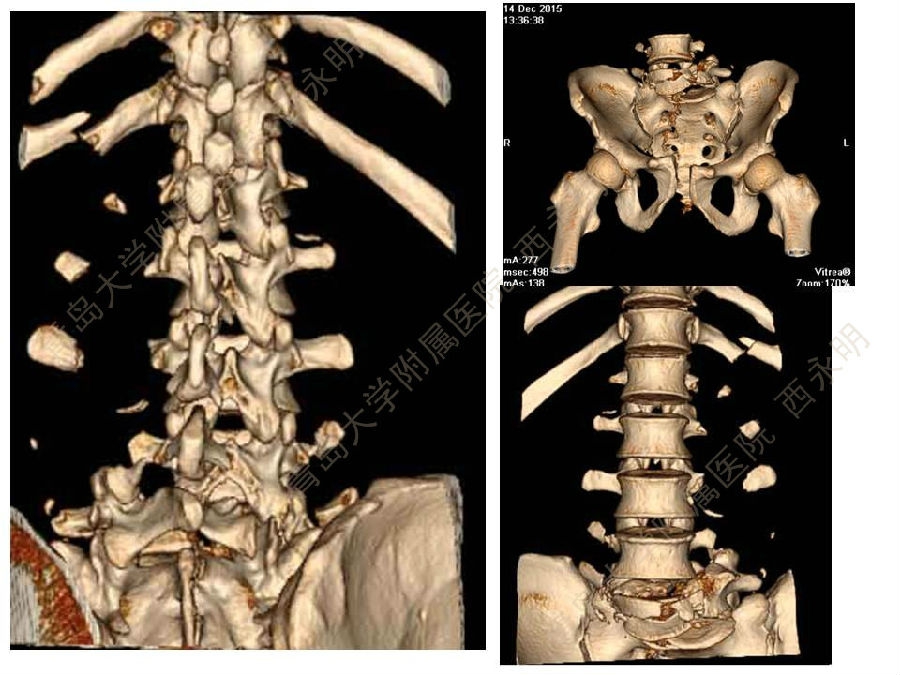

皮质骨螺钉技术及临床应用

颈椎伤病、脊柱畸形和脊柱肿瘤以及颈胸腰椎退变性疾病的微创治疗。长期从事临床一线的医、教、研工作,在多年的临床实践中积累了丰富的经验,并形成了以脊柱外科为专业方向,以颈椎外科、脊柱畸形和脊柱肿瘤为专业特色。